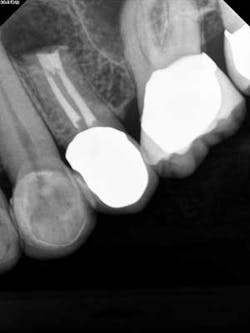

Case report A healthy 61-year-old female presents with a chief complaint of pain and discomfort in the upper left quadrant. A radiograph revealed a large radiolucency at the apex of tooth No. 12. An irregular root apex was also noted. Clinically No. 12 was sensitive to percussion and palpation in the buccal vestibular area. There was no response to cold. Diagnosis was necrotic tooth No. 12 with associated periapical abscess. RCT was recommended and the patient was referred to a specialist for completion. RCT was completed — no complications were noted and the prognosis was given as good. (Figs. 1 and 2) The patient was placed on recall by the endodontist for reevaluation of the lesion in 12 months.Fig 1. Fig. 2Eight months later, the patient presented back to the office stating that she felt pressure again in the upper left area. A radiograph of No. 12 showed an increased radiolucency around the apex of tooth No. 12. Furthermore, there was a draining fistula in the buccal vestibule. Diagnosis was persistent infection/disease, likely due to the initial presentation and presence of the cyst. (Fig. 3)